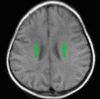

Figure 4. T1W image shows diffuse symmetrical, bilateral hypointensities with preponderance of frontal lobes (green arrows).

T1W image: T1-weighted image